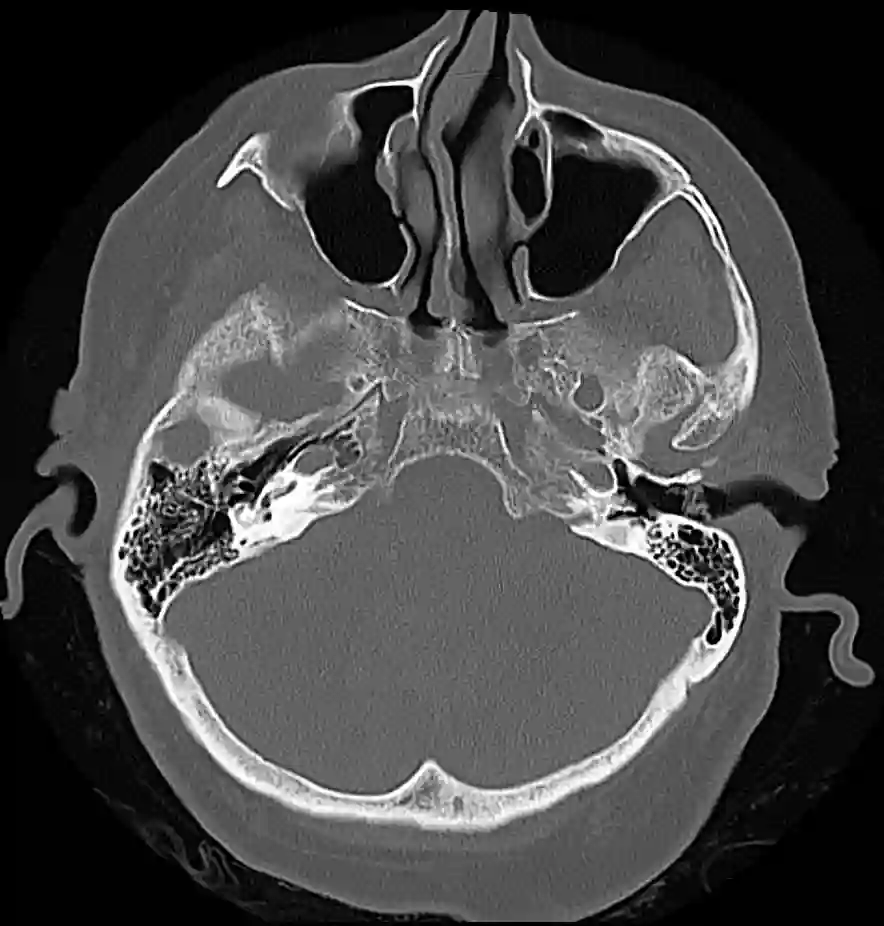

Abbildung

Bildgebung